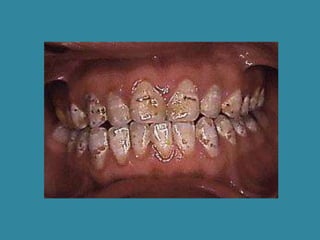

Tipo Hipocalcificado

Este subgrupo de amelogenesis imperfecta es una aberración

heredable en la formación del esmalte en la fase de calcificación.

El esmalte hipocalcificado es blando y frágil, en particular en las

regiones incisales, y se fragmenta con facilidad, con exposición

de la dentina subyacente, situación que produce un aspecto

desagradable.

El aumento de la formación de calculo y el retraso notable de la

erupción dental, son hallazgos constantes.

La mordida abierta anterior se observa en 60% de los casos que

muestran este defecto.